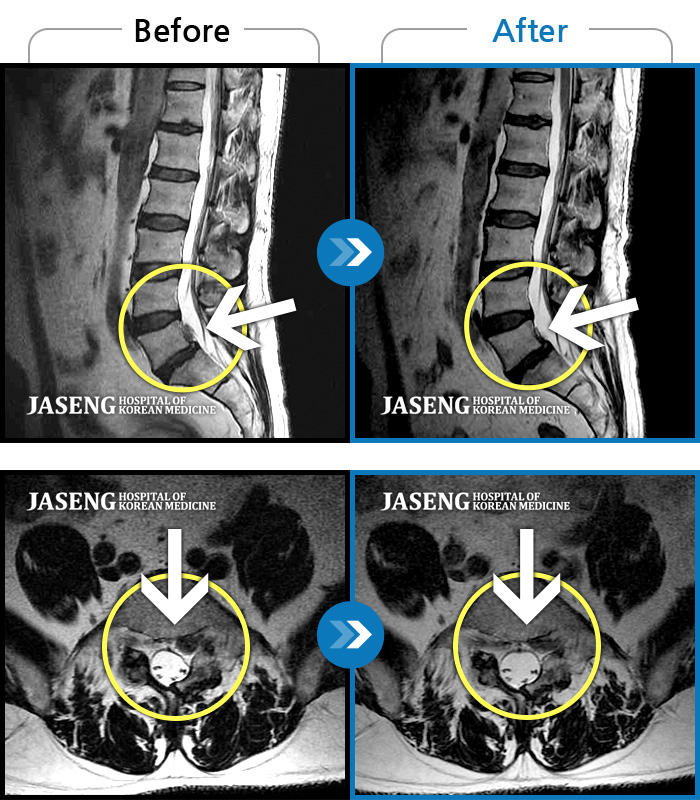

허리디스크

보라매 · 빈상은 원장

좌측 허리부터 고관절 통증이 심하고 다리까지 저려서 허리를 똑바로 펴기 힘들어요.

촬영시기

2020.07.27 ~ 2023.01.20

2023.11.24

조회수 514